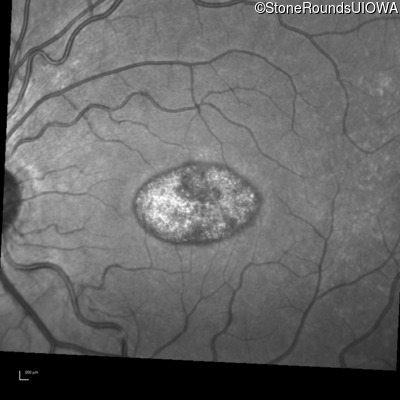

Infrared Fundus Photograph - Right - 20/32 sc

Exemplar